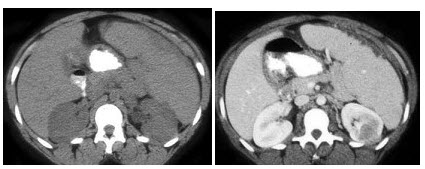

患者有镰刀形红细胞特征,结合图像,最可能的诊断为()

A、脾梗死

B、脾脓肿

C、脾出血

D、脾隔离症

E、以上都不是

D